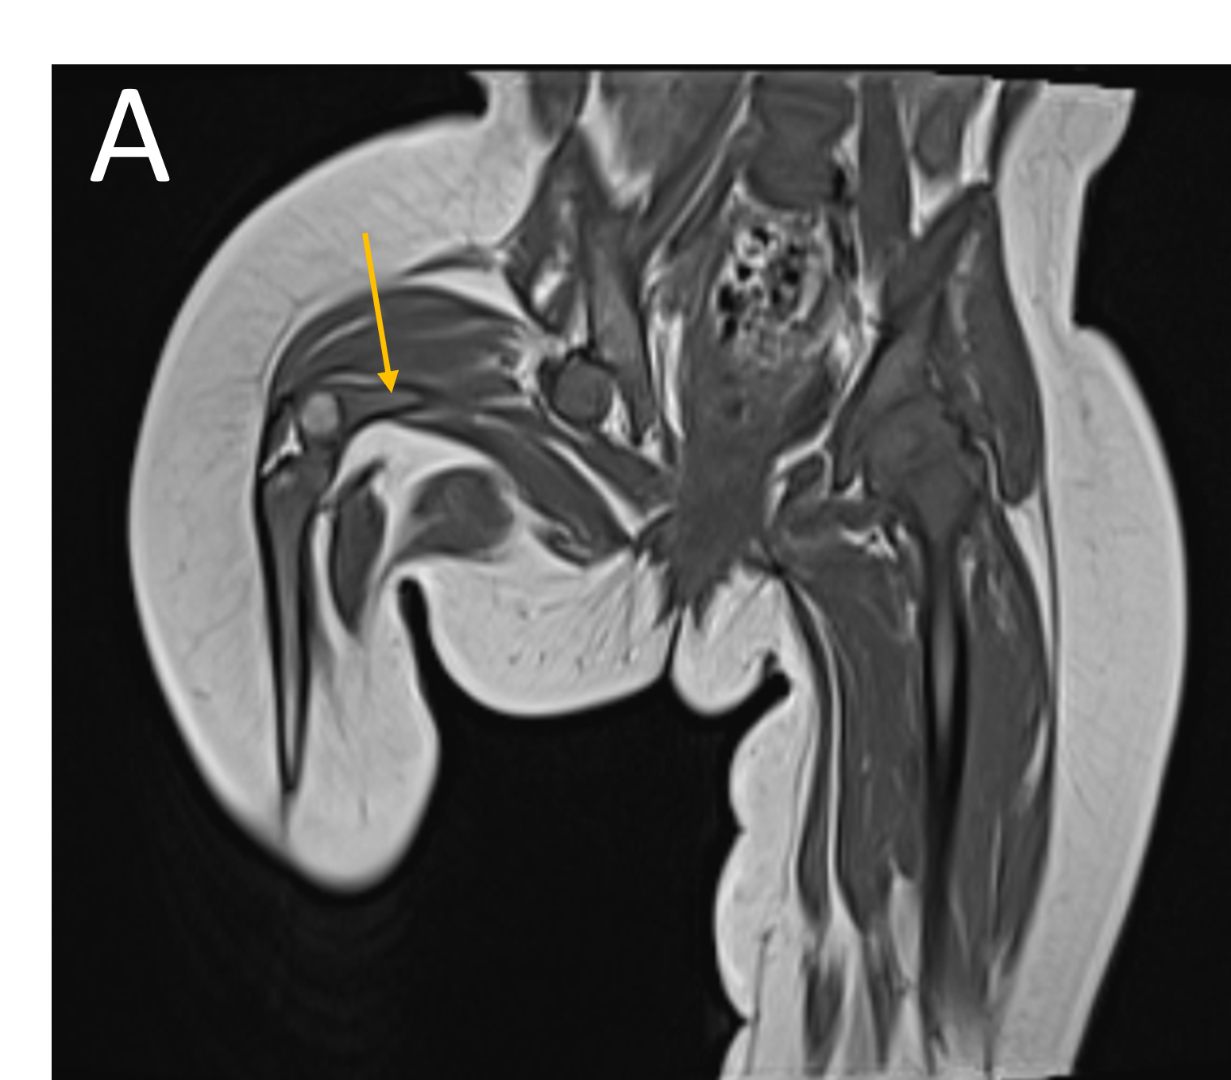

- A.LEGENDS – MR BILATERAL HIPS :Right femur is shortened, with a coxa vara deformity. Femoral shaft measures 7.2 cm in length. The acetabulum is moderately dysplastic and anteriorly rotated, But contains the femoral head. The femoral head and neck appear hypoplastic and posteriorly and externally rotated.

Bilateral Proximal focal femoral deficiency (class B on right side and class C on left side).